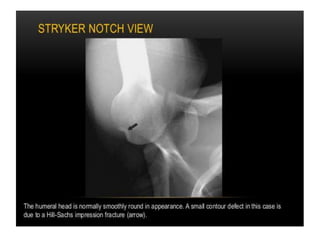

Stryker notch view

Plain radiographs • anteroposteriorview • axillary lateral view • supraspinatus outlet view

• 26.

AP VIEW Internal rotationExternal rotation Hill sach lesions Good view of GT & proximal humerusphysis Ture AP view (GRASHEY VIEW) Articular cartilage of glenoid and humeral head